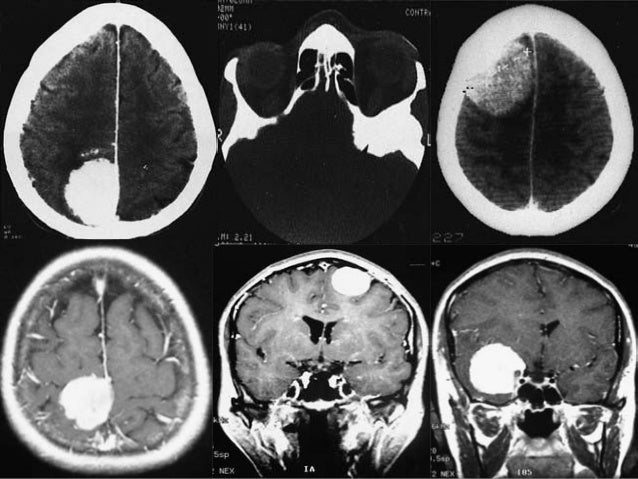

It is used to diagnose tumors, infection, inflammation, and other brain disorders. A biopsy means taking a small tissue sample from your brain and examining it under the microscope. A brain tumor is an abnormal growth of tissue in the brain or central spine that can disrupt proper a biopsy may be necessary, so a pathologist can be brought in to help identify the brain tumor type.

Specimens are taken from normal tissue, edema, solid tumor and central necrosis.

A stereotactic biopsy is a surgical procedure where a thin needle is inserted into the brain by a neurosurgeon to extract a small piece of tissue to examine. A biopsy is a major procedure, and it is the most definitive test for brain tumor diagnosis. A brain biopsy can help doctors diagnose brain illnesses, allowing them to devise treatment plans. These are generally seen in stereotactic biopsy: